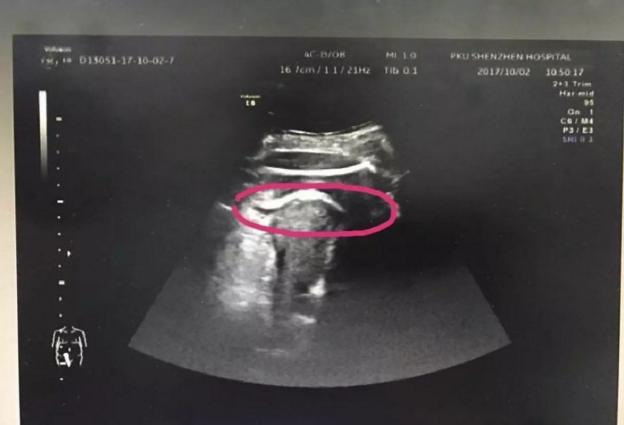

医生初步怀疑患者子宫破裂,当即安排做了B超。检查发现,胎儿的一条腿“踢破”了子宫,进入了腹腔,大腿根正卡在子宫壁上!

▲红色圆圈处是胎儿的腿,已经伸到子宫壁外